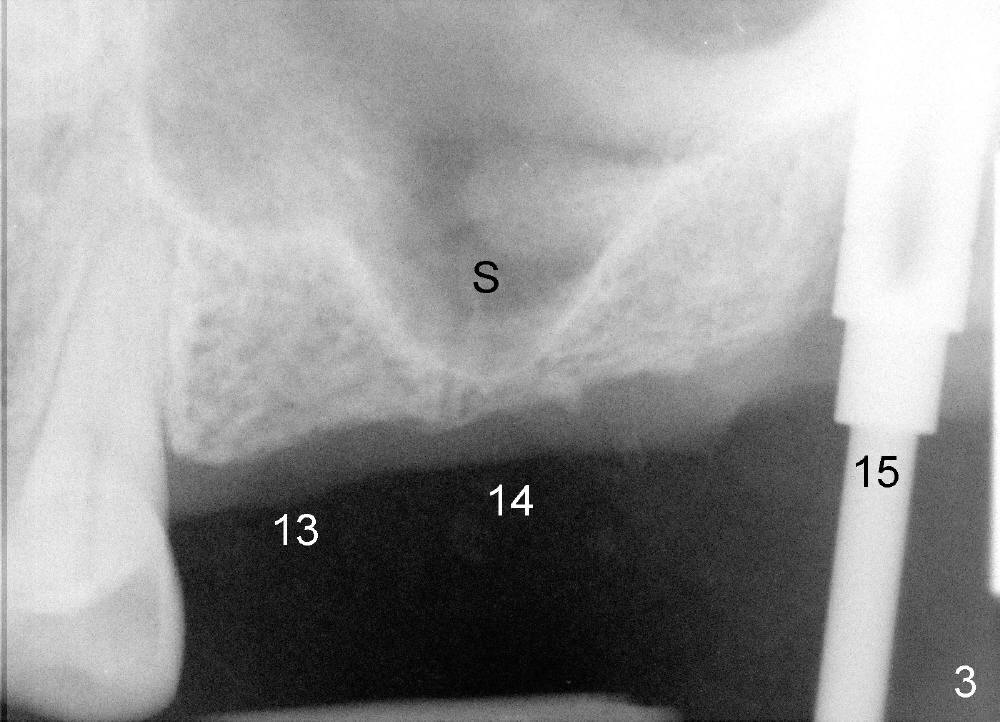

The two cases we discuss early appear to show that implants at the first molar are placed to engage in the mesial aspect of bone to have primary stability (1,2). But sometimes sinus floor may be right above the first molar (Fig.1-4). Fig.1 (CT sagittal) and 2 (coronal) were taken before #15 extraction, whereas Fig.3, 4 (PA) were taken during and immediately after extraction, respectively. A tapered 8x17 mm implant was placed at the site of #15.

In order to get primary stability, it is apparent that a large screw implant should be placed (Fig.1,2: 8x11 mm) to engage all of the lateral walls of the concave sinus floor (mesial and distal (Fig.1), buccal and lingual (Fig.2 B, L). Three millimeter shorter implant may be more appropriate (8x8 mm) in term of being less traumatic.

In fact, sinus graft has been tried without success (sinus membrane torn, buccal wall difficult to penetrate). The patient refuses to an offer to get a second trial by an expert such as Drs. Borgner and Dunson. Sinus lift appears to be more acceptable.